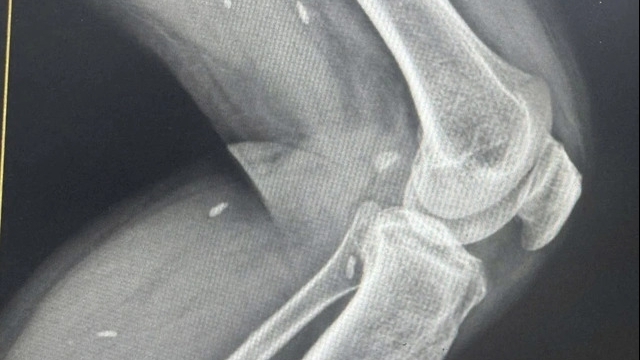

| Một trường hợp bệnh nhi tại khoa Cấp cứu – Bệnh viện Nhi Trung ương. Ảnh: BVCC |